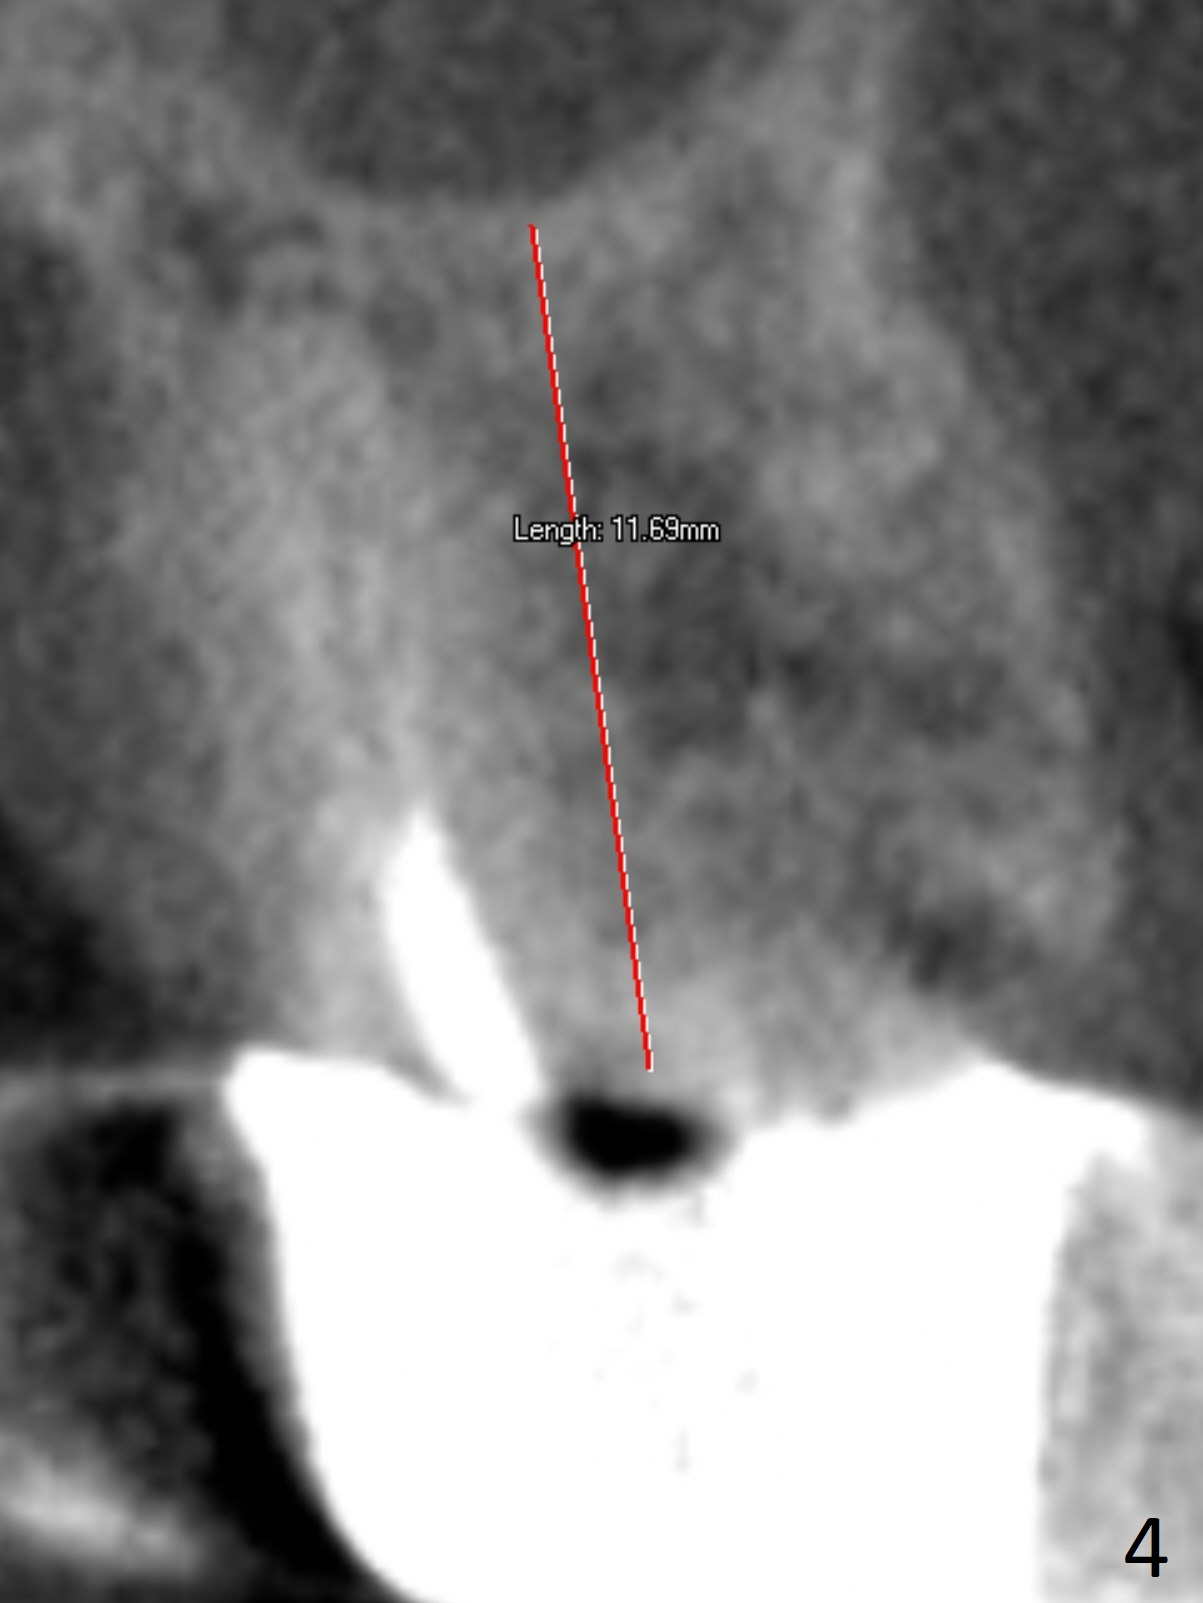

Soft Tissue Landmark for Osteotomy Depth

A 70-year-old woman fractures the crown at #14 (Fig.1).  A 5x11 mm implant will be placed at the septum (Fig.2).  Osteotomy depth can be determined using bony (Fig.3 with stopper) or gingival (Fig.4,5 with vision) landmark.  The CT was taken 5 years earlier.  Sagittal (Fig.6) and axial (Fig.7) sections confirm suitability of the 5x11 mm implant for the site.  Prepare surgical handpiece for sectioning the tooth for extraction.  After drills, use Magic Expanders for sinus lift.  Place Vanilla Graft prior to dummy implant(s).  A bone-level implant crown may be easier to be repaired if the proximal contact is not ideal.